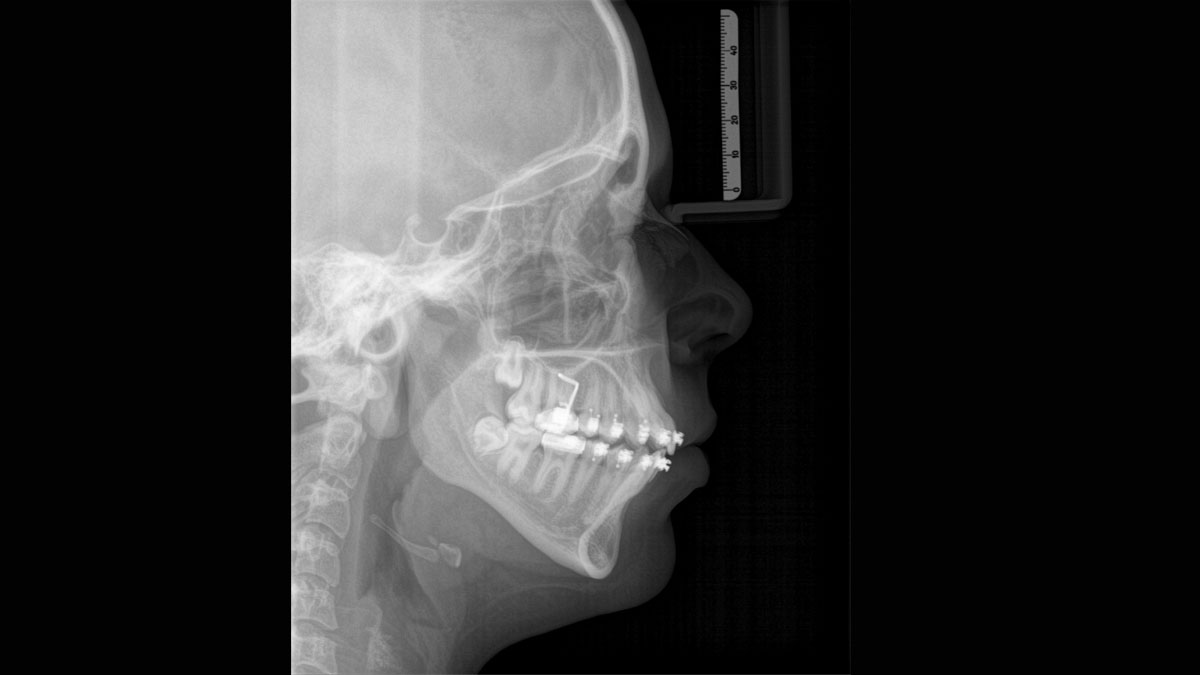

For exceptional panoramic images with high sharpness. You can choose an optional right or left cephalometric arm, which can be retrofitted at any time

Thanks to the optimised low dose mode with a dedicated filter, the imaging of dense structures, such as bones, is possible at a greatly reduced dose. This makes Intelligent Low Dose an attractive and efficient option for many clinical situations. Whether in orthodontics or implantology - with Dentsply Sirona solutions you will find the optimum setting for every case.